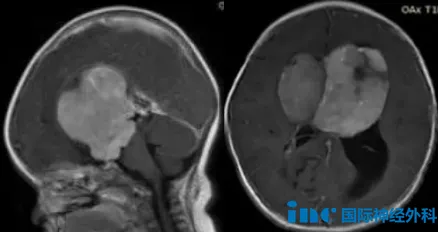

"首次看到孩子的MRI影像时,我感到震惊。"小橘母亲清晰记得那幅图像:巨大肿瘤占据婴儿狭小的颅腔。若不进行治疗,肿瘤将持续生长,最终压迫邻近脑组织,甚至危及生命。

多位专家达成共识:患儿很可能患有鞍区视神经胶质瘤,通常属于低级别或良性肿瘤,且治愈率较高。对于此类低级别胶质瘤,完全彻底的手术切除是首选治疗方法,这对解除脑部局部压迫至关重要。但手术同样伴随风险,包括垂体功能不全、视力障碍和中风等。若能实现最大程度的安全切除,预后生存率将非常理想,不会干扰正常生活。后续需要持续随访并接受适当治疗,预期寿命可与普通人群相当。但对复发率的评估需根据肿瘤级别和性质确定。

巴教授评估认为:针对该患者,可实现90%乃至更高的切除率。全切/近全切可能性与良好功能结局相关。手术风险与肿瘤血管特征有关,因患儿年龄小、血容量有限,需要精细的麻醉管理、熟练的手术团队配合,以及术中磁共振成像系统(iMRI)、术中神经电生理监测、术中神经导航等高精尖设备提供支持。